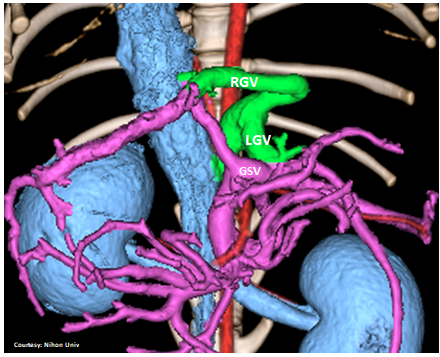

“LGHV +RGV”

Left Gastric – Left Hepatic Vein shunt with Right Gastric Vein Contribution

Courtesy: Nihon Univ